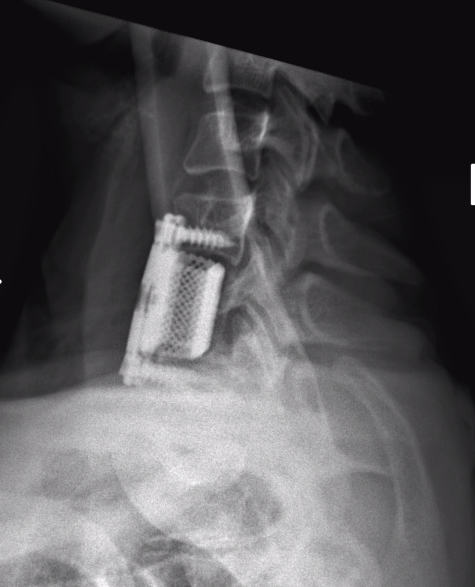

Lateral

- > 50% anterior column loss of height

- loss of posterior vertebral height

A. Anterior corpectomy & fusion with tricortical graft + plate

B. Anterior corpectomy & fusion with mesh cage + bone graft + plate

+/- Supplemental posterior fixation / cervical lateral mass screws

Anterior corpectomy and tricortical graft